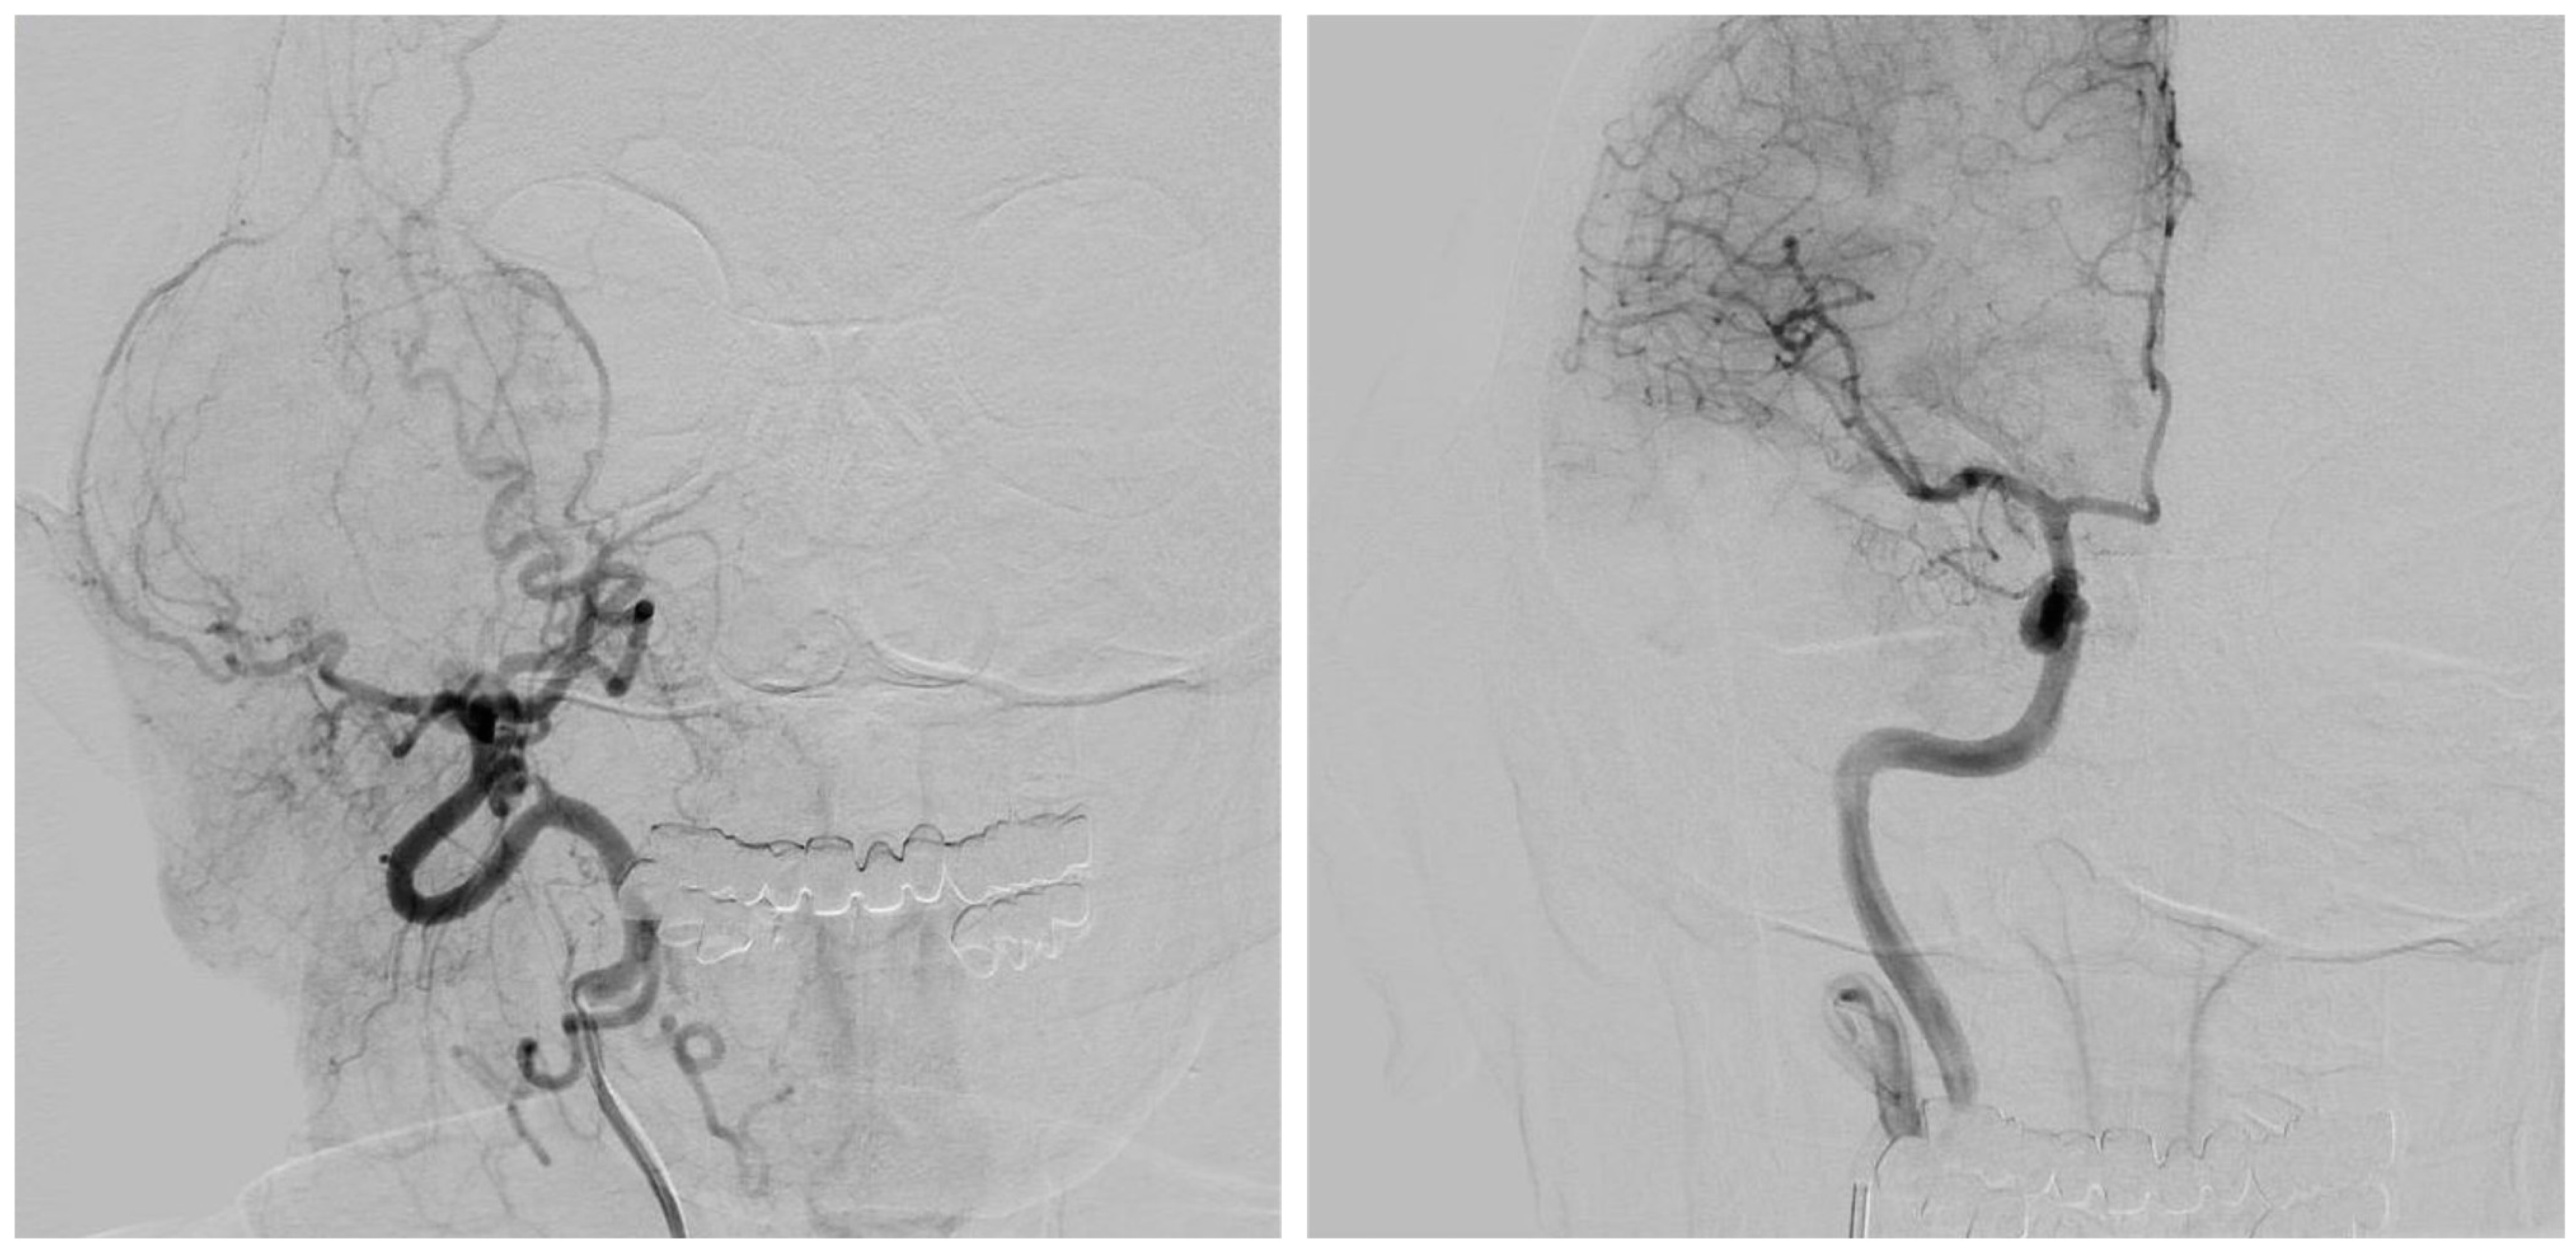

- Vascularization: Being a particularly delicate area considering the vascular and other structures present in the area, these must be identified. Medially to the glenoid fossa, besides the internal maxillary artery, there are the foramen ovalis, through which there is the mandibular nerve V3 (third division of the trigeminal nerve CN V), and the the foramen spinosum, which gives passage to the middle meningeal artery. Posteromedially instead, there are the foramen lacerum; the carotid canal, which contains the internal carotid artery; the jugular hole, which gives passage to the glossopharyngeal nerve (CN IX), vagus nerve (CN X), and accessory nerve (CN XI), and in its posterolateral originating from the sigmoid sinus, gives rise through the hole to the internal jugular vein; the stylomastoid hole, which contains the stylomastoid artery and the facial nerve (CN VII). So, to segment and reconstruct arterial vasculature, a 3D time-of-flight (TOF) MRI with the following parameters was acquired: TR = 25.0 ms; TE = 7.15 ms; slice thickness = 0.5 mm; in-plane resolution: 0.4 × 0.4 mm; slice GAP = −25%; matrix 256 × 256 px. To highlight venous structures, a phase-contrast MR venography sequence was performed.

- Computed Tomography Angiography (CTA): When a free bone flap was planned (e.g., free fibula flap, free iliac crest flap, etc.) in order to perform a mixed autologous/alloplastic eTMJR, the patient underwent a CTA, given the need to know the anatomy of the vascular pedicle.